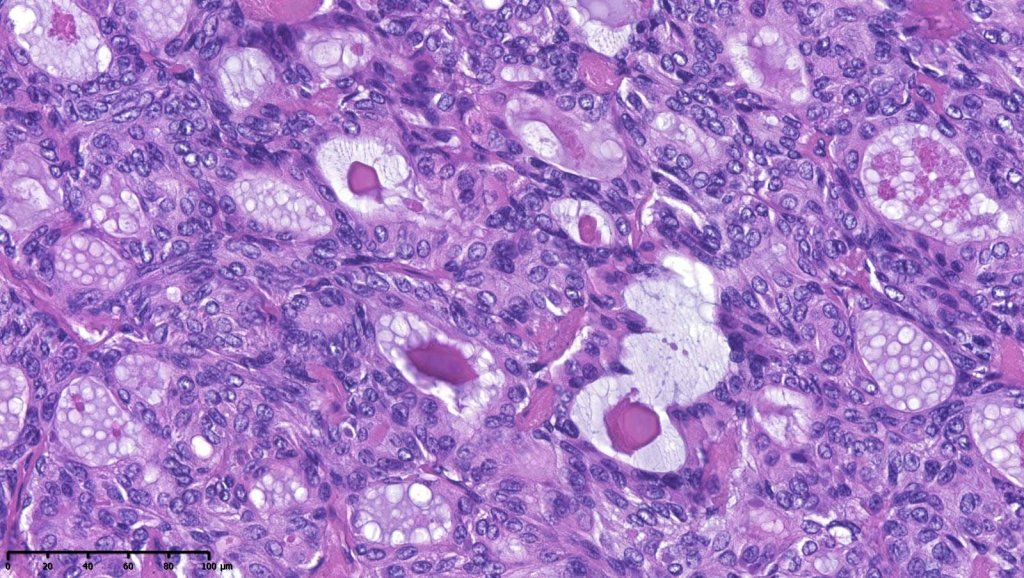

Histological features

•Generally composed of an admixture of small eosinophilic cells & glycogen-rich larger clear cells

•Round to oval vesicular nuclei with small nucleoli or hyperchromatic nuclei

•Ductal and glandular differentiation

•Rarely sebaceous differentiation

•Hyaline collagenous stroma